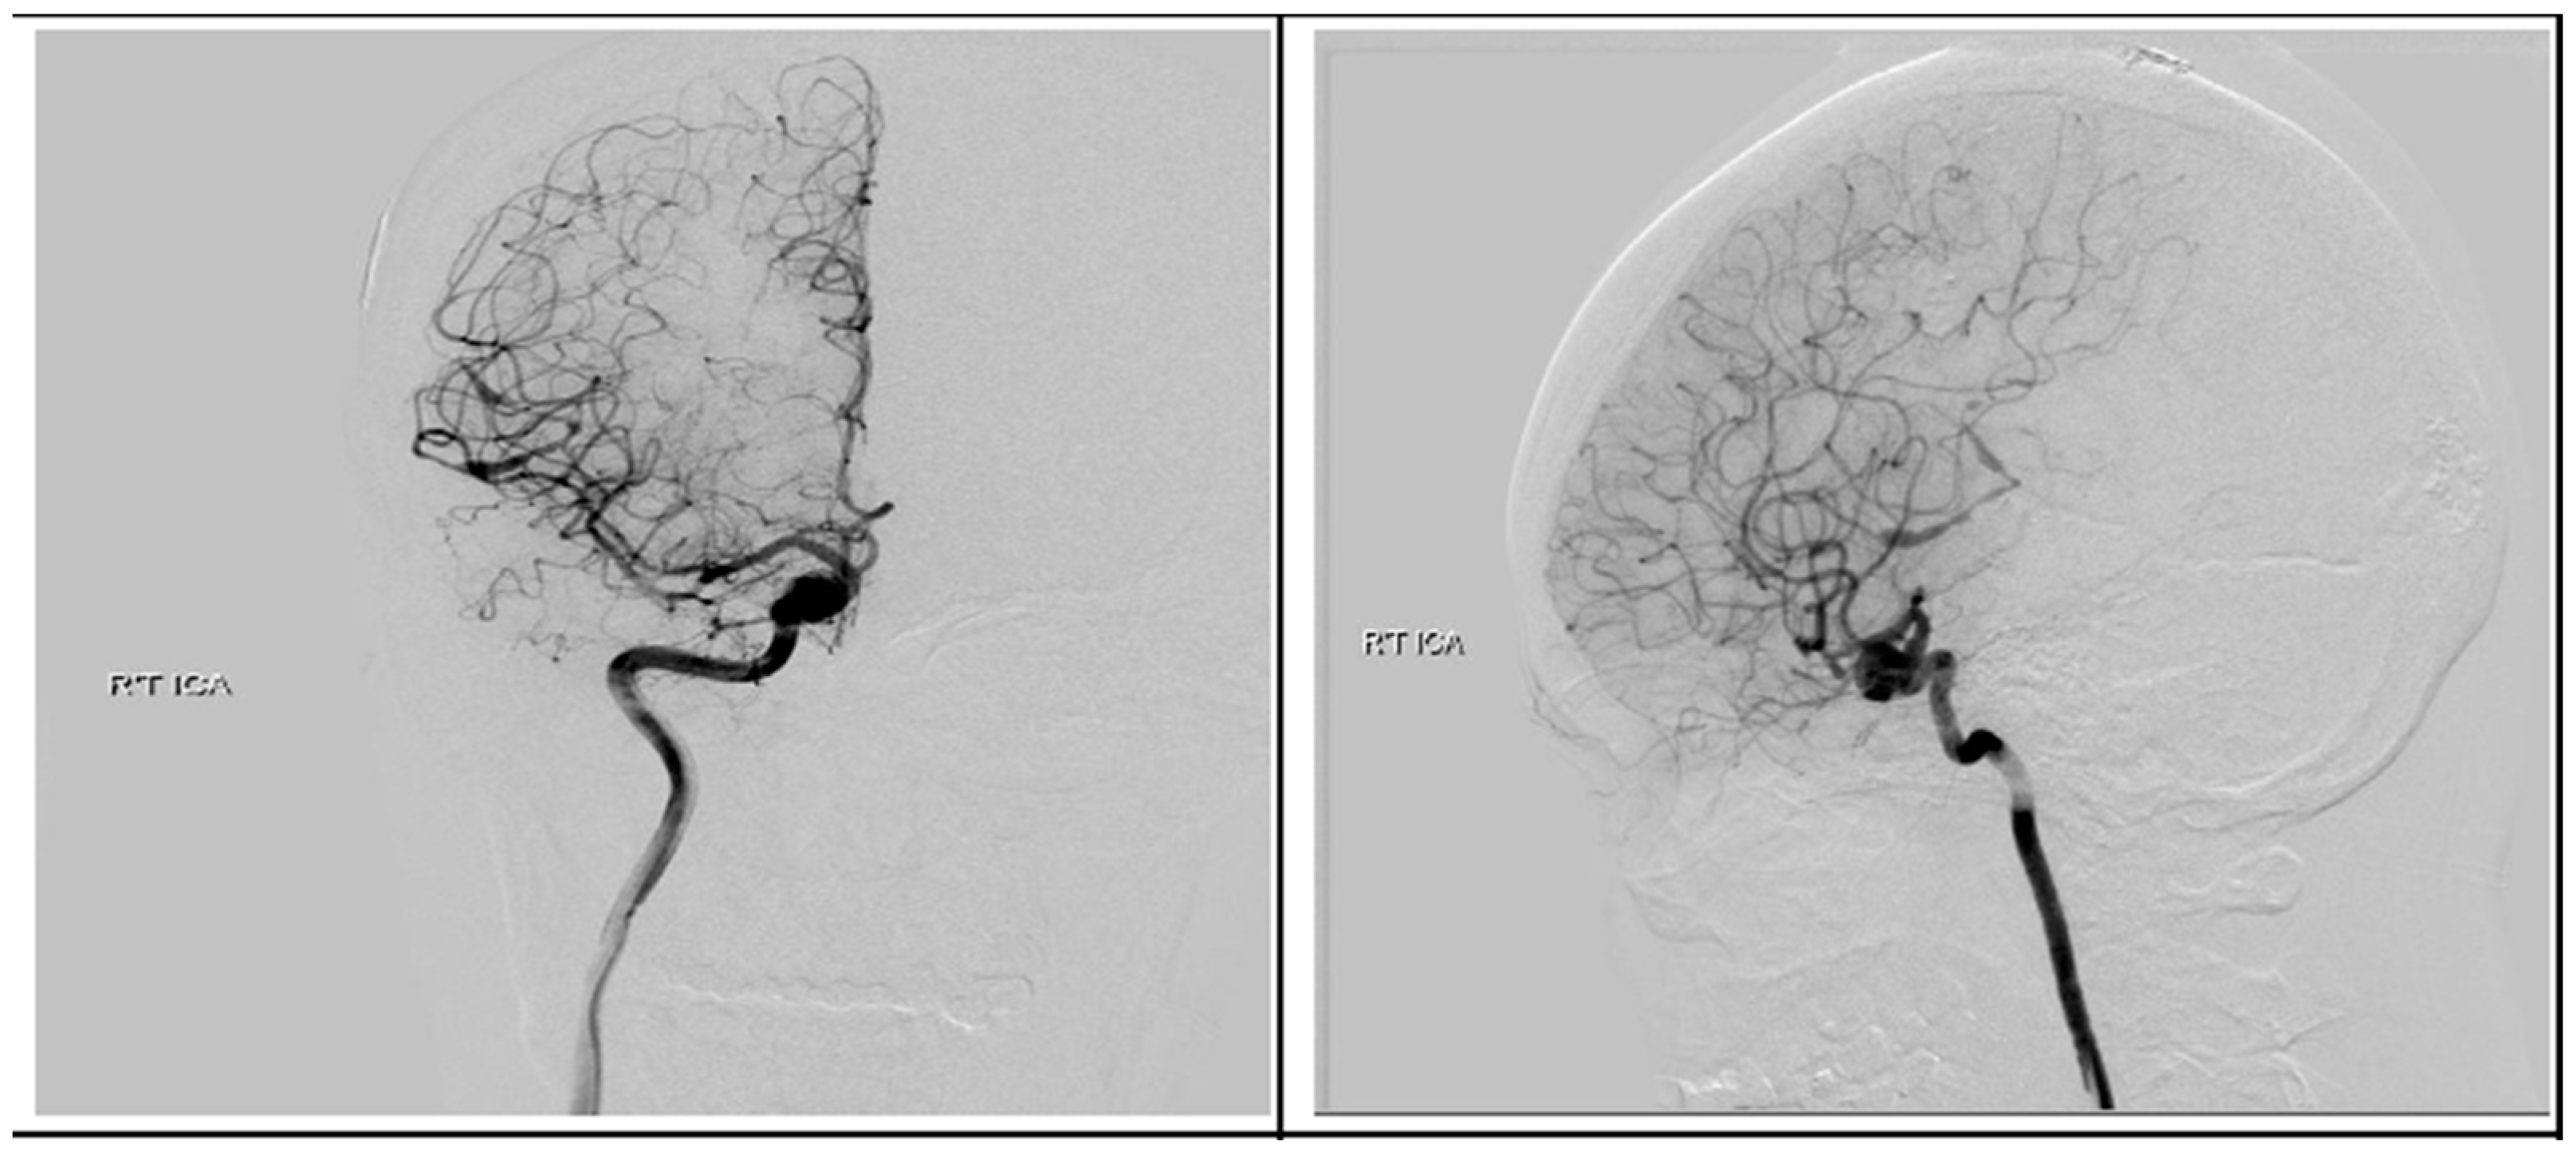

Following discharge, she underwent concurrent chemoradiotherapy with a total dose of 6900 cGy given in 30 fractions in conjunction with temozolomide (TMZ) at 75 mg/m2 daily. Upon a follow-up visitation 6 months post-operation, apart from previous neurologic deficits, she remained in good condition. Surveillance imaging showed no disease progression in the past 18 months after the surgery. We performed digital subtraction angiography (DSA) 4 months later and found no evidence of AVM, but the ICA aneurysm revealed only a sparse change in size without a sign of rupture Figure 9. After a detailed discussion with the patient and her family members, they decided to treat the aneurysm with endovascular intervention.

Figure 9.

Postoperative digital subtraction angiography. Angiography revealed a right supraclinoid internal carotid artery aneurysm.

Regarding the present case, we expected that the supra-clinoid aneurysm would reduce in size after removal of the ipsilateral AVM and glioblastoma due to intracranial hemodynamic changes and fewer angiogenesis-stimulation factors such as VEGF from the tumor. A similar hypothesis was addressed in the current literature and demonstrated good outcomes in cases where intracranial aneurysms and brain tumors simultaneously coexisted [13,14], but unfortunately the postoperative DSA revealed only sparse change in the right ICA aneurysm in the present case. Therefore, the patient still needed to receive intervention involving flow diverter stent placement.